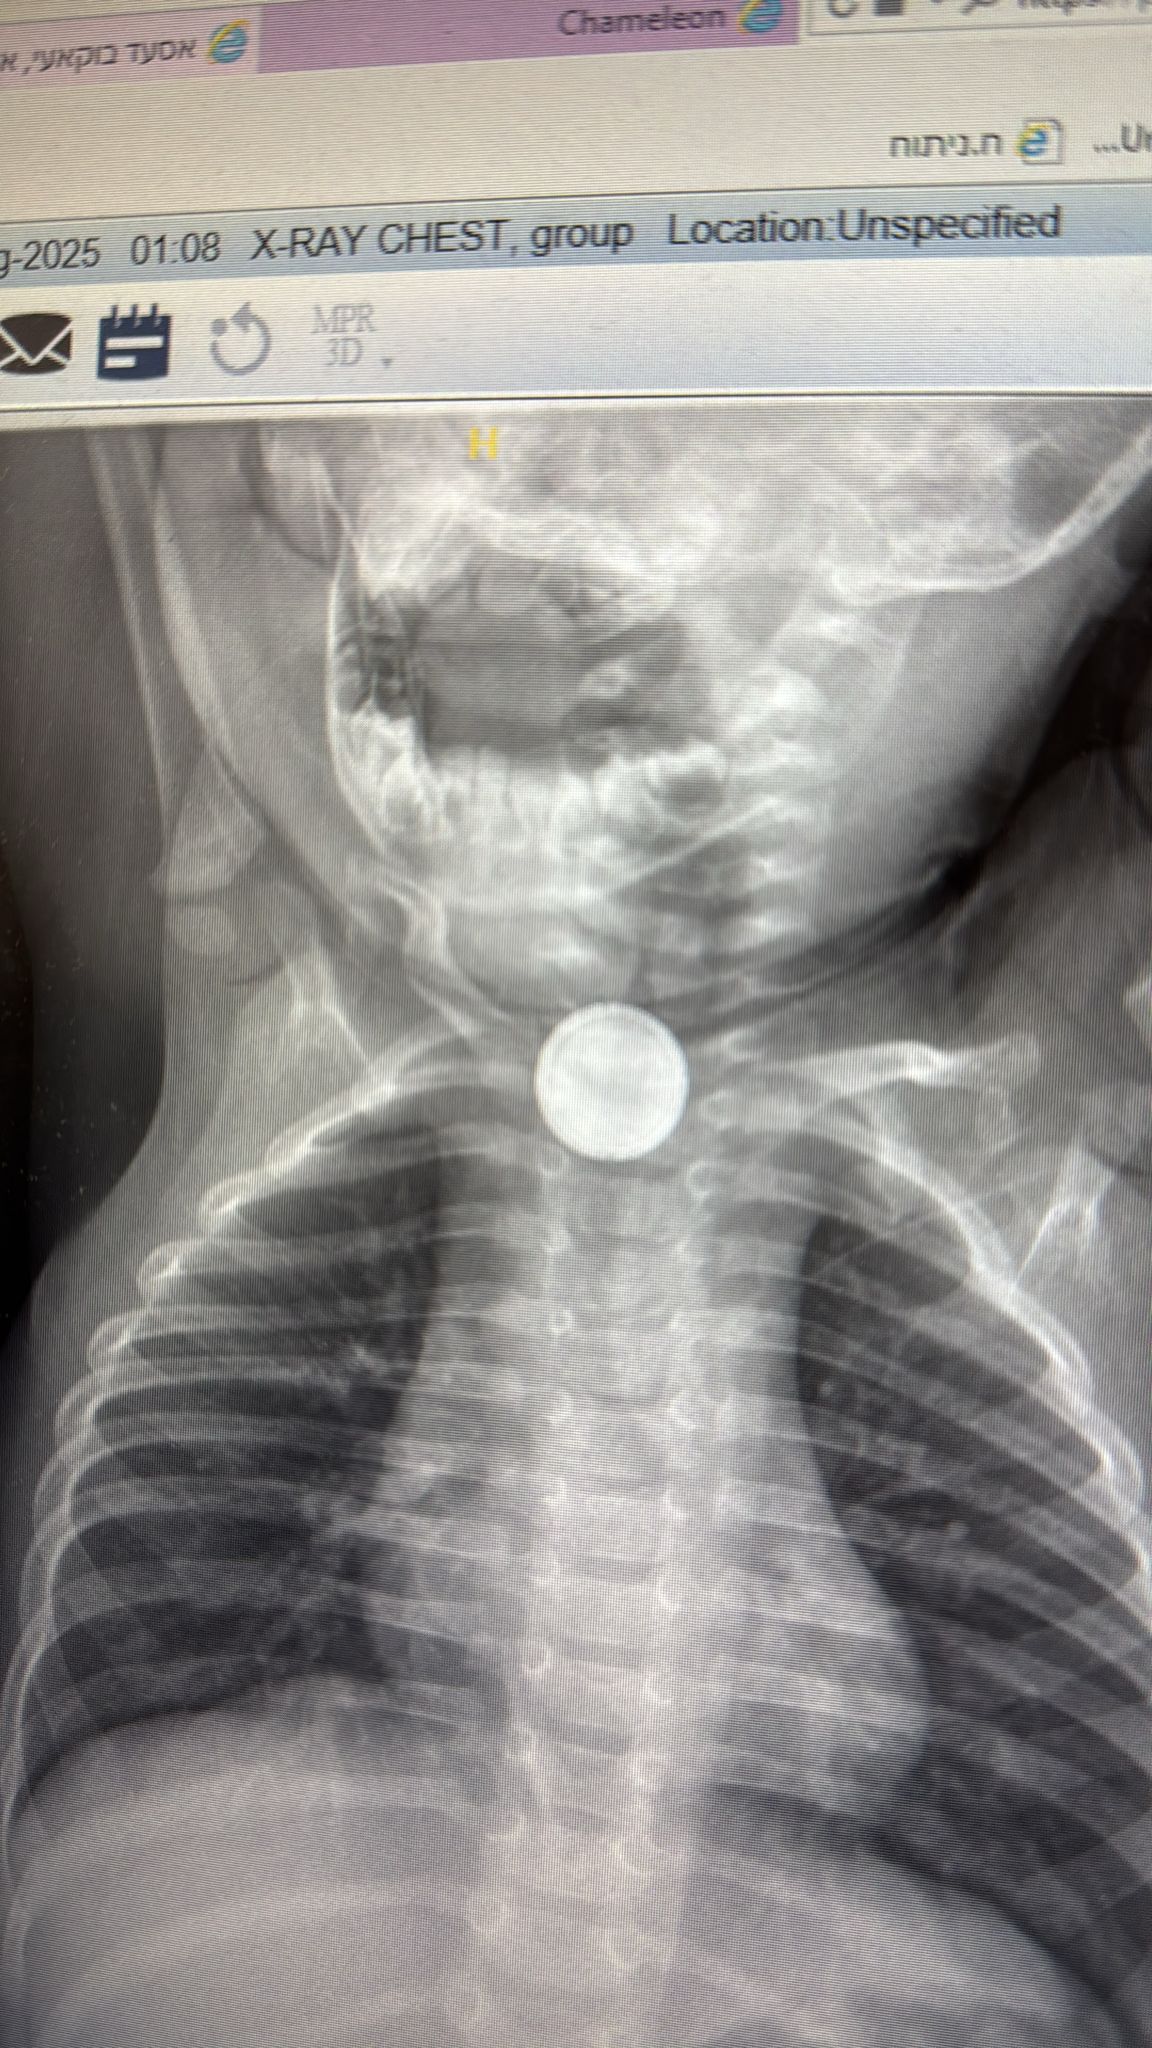

صورة الأشعة السينية العاجلة التي أُجريت كشفت وجود جسم دائري غريب عالق في المريء، بدا بالفعل أنه بطارية. ومن هنا أصبح الوقت حرجا للغاية، إذ أن بقاء البطارية عالقة في المريء قد يؤدي إلى أضرار فورية، وأحيانا غير قابلة للعلاج.

تصوير مكتب الناطق بلسان المركز الطبي للجليل